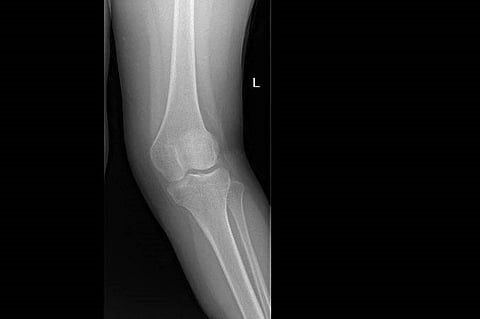

نجح فريق طبي في قسم جراحة العظام والتخدير والعمليات بمستشفى الملك خالد ومركز الأمير سلطان للخدمات الصحية بالخرج، بقيادة الاستشاري خالد سليمان، في إنهاء معاناة فتاة سعودية تعاني من تشوه في الركبة اليسرى واعوجاج خارجي (ركبة فحجاء) وعرج عند المشي.

وتم استقبال المريضة في عيادة العظام، وبعد عمل الأشعة المطلوبة والفحوصات اللازمة، وُضعت خطة علاجية من قبل الفريق الطبي المعالج وأجريت العملية للمريضة باستخدام تخدير نخاعي (نصفي)، وتم إصلاح اعوجاج عظمة الفخذ وعظمة الساق والتشوه بالركبة اليسرى، وتكللت العملية بالنجاح.

يذكر أن هذه العملية تعتبر من العمليات التخصصية المتقدمة في جراحة العظام.